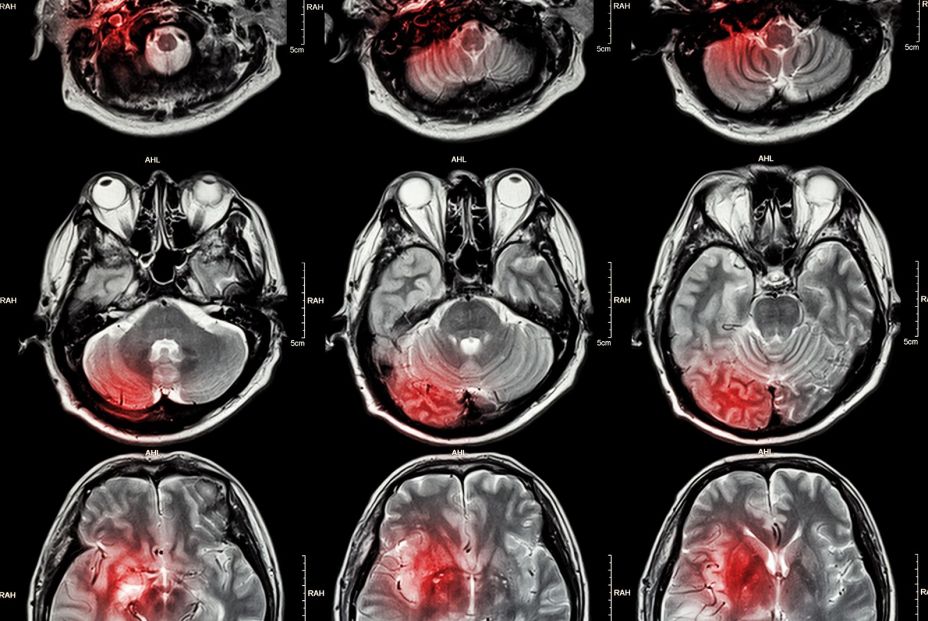

El cerebro adulto promedio pesa solo alrededor de 1, 36 kg, pero es uno de los órganos más complejos y vitales del cuerpo humano. La cognición a menudo disminuye y nuestros cerebros se vuelven propensos a las enfermedades a medida que envejecemos, por lo que, a medida que los avances médicos y otros factores ayudan a que la población mundial viva más tiempo, la prevalencia de enfermedades cerebrales, incluida la demencia, está aumentando. Sin embargo, mantener el cerebro sano puede ser más fácil de lo que la gente cree con algunos consejos útiles de la American Heart Association (AHA, de sus siglas en inglés)

La salud cerebral adecuada incluye la capacidad funcional de realizar todas las diversas tareas de las que es responsable el cerebro, como pensar, moverse y sentir. Muchos factores de riesgo modificables de pérdida cognitiva, como una dieta poco saludable y un estilo de vida sedentario, se desarrollan ya en la infancia y la adolescencia. A medida que envejecemos, nuestra capacidad de recordar, resolver problemas, pensar y comunicarnos disminuye.

"Ahora sabemos que muchos de los mismos factores de riesgo de salud que causan enfermedades cardiovasculares e ictus contribuyen a un deterioro de la salud cerebral general", ha declarado en un comunicado Mitchell S. V. Elkind, director científico clínico de la AHA. Y ha insistido: "Al igual que ocurre con las enfermedades cardíacas y los derrames cerebrales, la mayoría de las enfermedades cerebrales se pueden prevenir. Sin embargo, la combinación del envejecimiento de la población y los aumentos sustanciales previstos en la presión arterial alta, la obesidad y la diabetes probablemente conduzcan a un crecimiento sin precedentes en muchos tipos de enfermedades cerebrales".